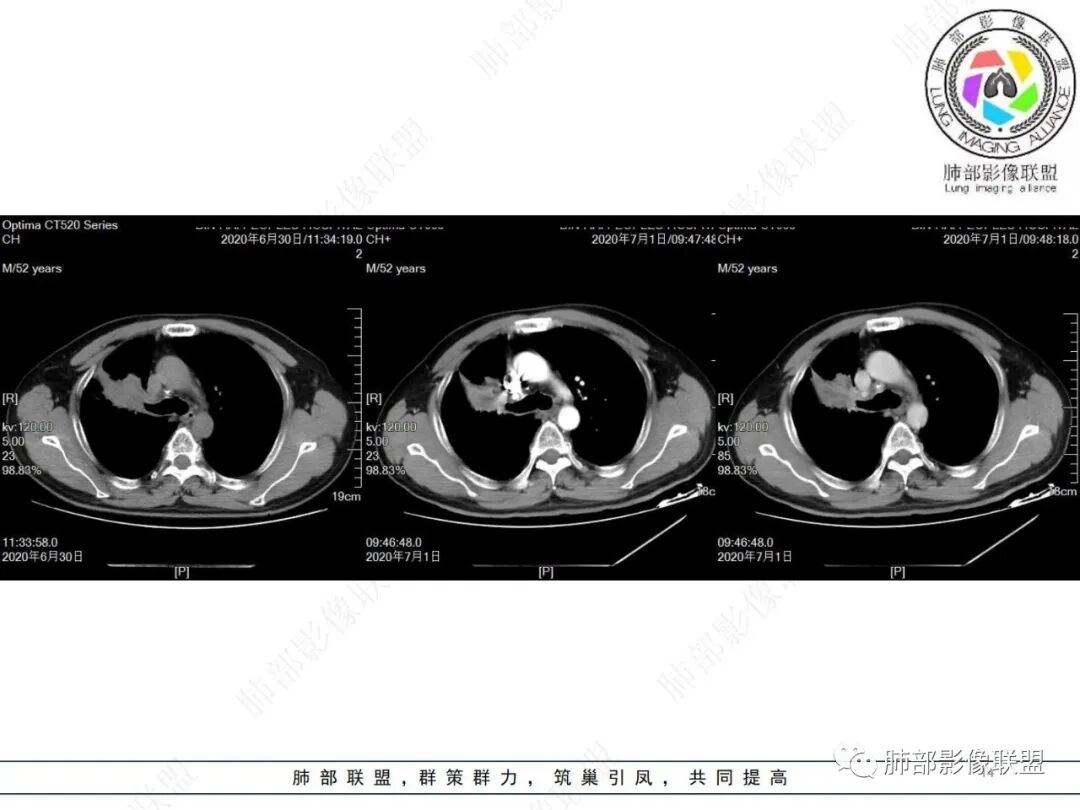

右肺上叶不规则形软组织密度肿块影,边缘见分叶,毛刺,病灶呈宽基底与胸膜相连,病灶内见坏死,增强扫描呈不均匀性强化,右肺上叶支气管截断,纵隔内见肿大淋巴结,肿瘤标志物增高,考虑鳞癌可能,鉴别小细胞癌,腺癌。

老年人,右肺上叶肺不张伴阻塞性炎症,右肺上叶支气管闭塞,增强病灶强化不均匀,可见边缘不清晰的坏死,纵膈淋巴结增大,考虑中央型肺癌,鳞癌可能性大。

右肺上叶不规则肿块,分叶、毛刺,上叶支气管截断,断端圆钝,不均匀强化,其内空泡及坏死,坏死边界不清,考虑腺癌或腺鳞癌,鉴别鳞癌

除了年龄,吸烟,湖泊样坏死符合鳞癌,其他都不符合,支气管截断,不在肿块中央,远处也没有明显阻塞样改变,更像爬行后截断,肿瘤标志物CEA高得厉害,其他鳞癌标志物并不高。这种坏死,低分化腺癌一样常见,强化远端也有强化,不符合鳞癌,所以我考虑低分化腺癌(伴或不伴有神经内分泌分化)或者肉瘤样癌。

边缘都是强化的肿瘤组织,鳞癌是不会这样的,符合腺癌

不符合鳞癌有四点:1,截断的支气管不在肿块中央,而是外朝内爬行(肿块外缘大于近端)2、支气管截断在前段,前段远端没有阻塞性改变。3、鳞癌是近端强化,远端为阻塞性的不强化粘液栓或明显强化的不张肺组织,这个是中间坏死,周围强化的肿瘤组织。4、肿瘤标志物CEA增高太明显,鳞癌标志物不高。